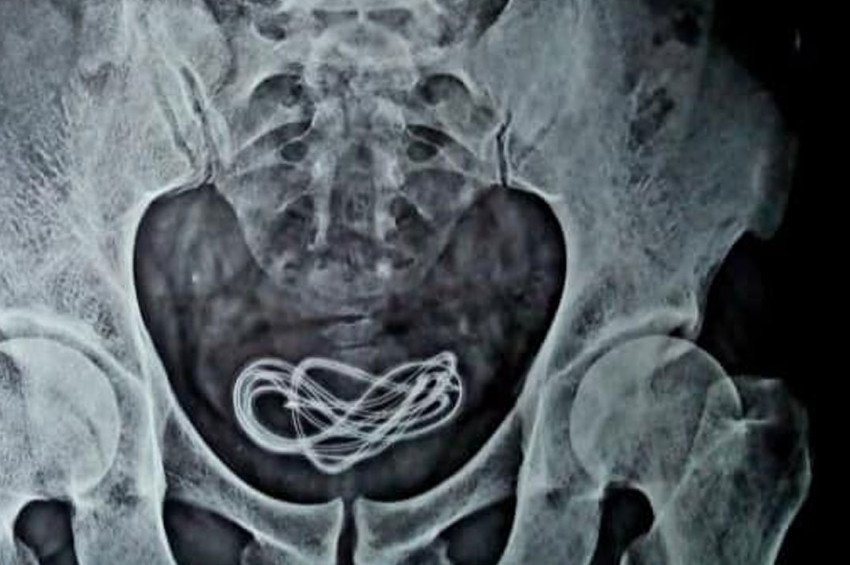

Doktorlar tarafından röntgeni çekilen adamın röntgen sonuçlarını inceleyen doktorlar, fazlasıyla şaşırtıcı bir şeyle karşılaştılar. Karın ağrısı şikayetiyle hastaneye başvuran adamın içinde tam 61 santimetre uzunluğunda bir kablo gözüküyordu. Doktorlar, hemen hastayı tedavi altına aldılar.

Mesanesinde 61 santimetrelik kabloyla dolaşan adamın mide-bağırsak kanalı, doktorlar tarafından incelenecekti. Ancak hasta, bunun öncesinde tam iki gün boyunca kabızlık ilacı kullandı. Hastanın mide-bağırsak kanalını inceleyen doktorlar, burada bir şey bulamamıştı. Çünkü kablo, adamın mesanesinde bulunuyordu. Yani cinsel organından bir şekilde içeri girmişti. Bunu gören doktorlar, hemen ameliyat kararı aldılar.